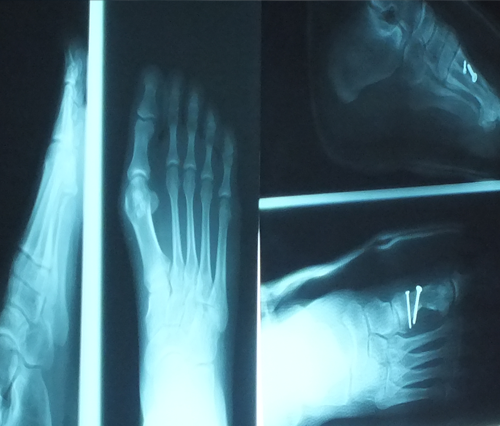

Fractures (breaks) are common in the foot including the fifth metatarsal - the long bone on the outside of the foot that connects to the little toe. Anyone who has symptoms of a fracture should see a foot and ankle surgeon as soon as possible for proper diagnosis and treatment. To arrive at a diagnosis, the surgeon will ask how the injury occurred or when the pain started. The foot will be examined, with the doctor gently pressing on different areas of the foot to determine where there is pain. The podiatrist will also order x-rays and determine appropriate treatments.